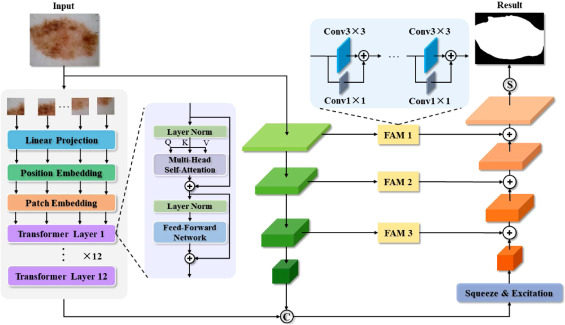

FAT-Net

Paper: 《FAT-Net: Feature Adaptive Transformers for Automated Skin Lesion Segmentation》

Accepted by MIA 2021.

FAT-Net 属于最早期应用 Transformer 架构的经典医学图像图像分割网络,致力于解决皮肤病变分割任务。整个网络基于编解码架构,编码器部分采用 Transformer + CNN 的并行双分支架构进行主要的特征提取,以有效地捕获远程依赖关系和全局上下文信息。随后,基于特征重标定的策略对来自不同架构所提取到的的特征图进行更深层次的融合,通过学习的方式来自动获取到每个特征通道的重要程度,最后再筛选出更加有用的特征图。最后,通过在跳跃连接部分集成了特征自适应模块(FAM)来激活有效通道和抑制不相关的背景噪声,从而增强相邻层特征之间的特征融合。